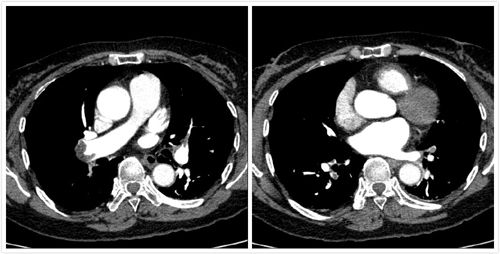

患者,女性,62歲,曾從事油漆工工作,工作有長時間站立、下蹲特點。因活動后胸悶、氣短、呼吸困難3日,加重1日主訴入院,入院后經(jīng)心內(nèi)二科張曉鋒主任、呂強副主任醫(yī)師仔細(xì)分析患者癥狀及心電圖、血氣分析后,肺動脈CTA檢查迅速明確診斷,確定該患者介入手術(shù)適應(yīng)證,預(yù)計會有較好的療效。在充分與患者及家屬溝通,同意肺動脈造影及抽栓、碎栓、藥物溶栓手術(shù)治療。呂強副主任醫(yī)師、張曉鋒主任醫(yī)師、潘立棟醫(yī)師、邵玉玲主管護師、車曉偉技師組成的手術(shù)小組在經(jīng)歷一個多小時緊張而有條不紊的操作后,順利完成了肺動脈血栓抽栓、碎栓、藥物溶栓搶救。患者術(shù)后取得了立竿見影的效果,胸悶、氣短、呼吸困難明顯減輕,次日復(fù)查動脈血氣分析氧分壓明顯改善,目前患者恢復(fù)良好。

△ 溶栓前

△ 溶栓后